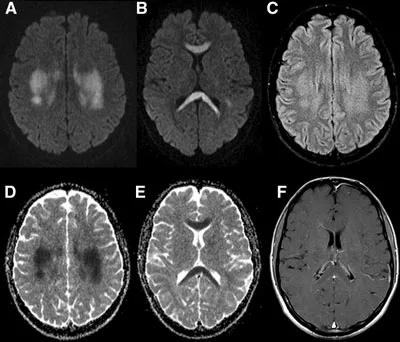

31岁,男性,长期饮酒,出现急性失语、短期注意力和记忆力缺陷,胼胝体及半卵圆中心对称性异常信号,扩散受限,未见强化,经过维生素B1/6/9/12治疗后病灶吸收明显,诊断为原发性胼胝体变性急性期。